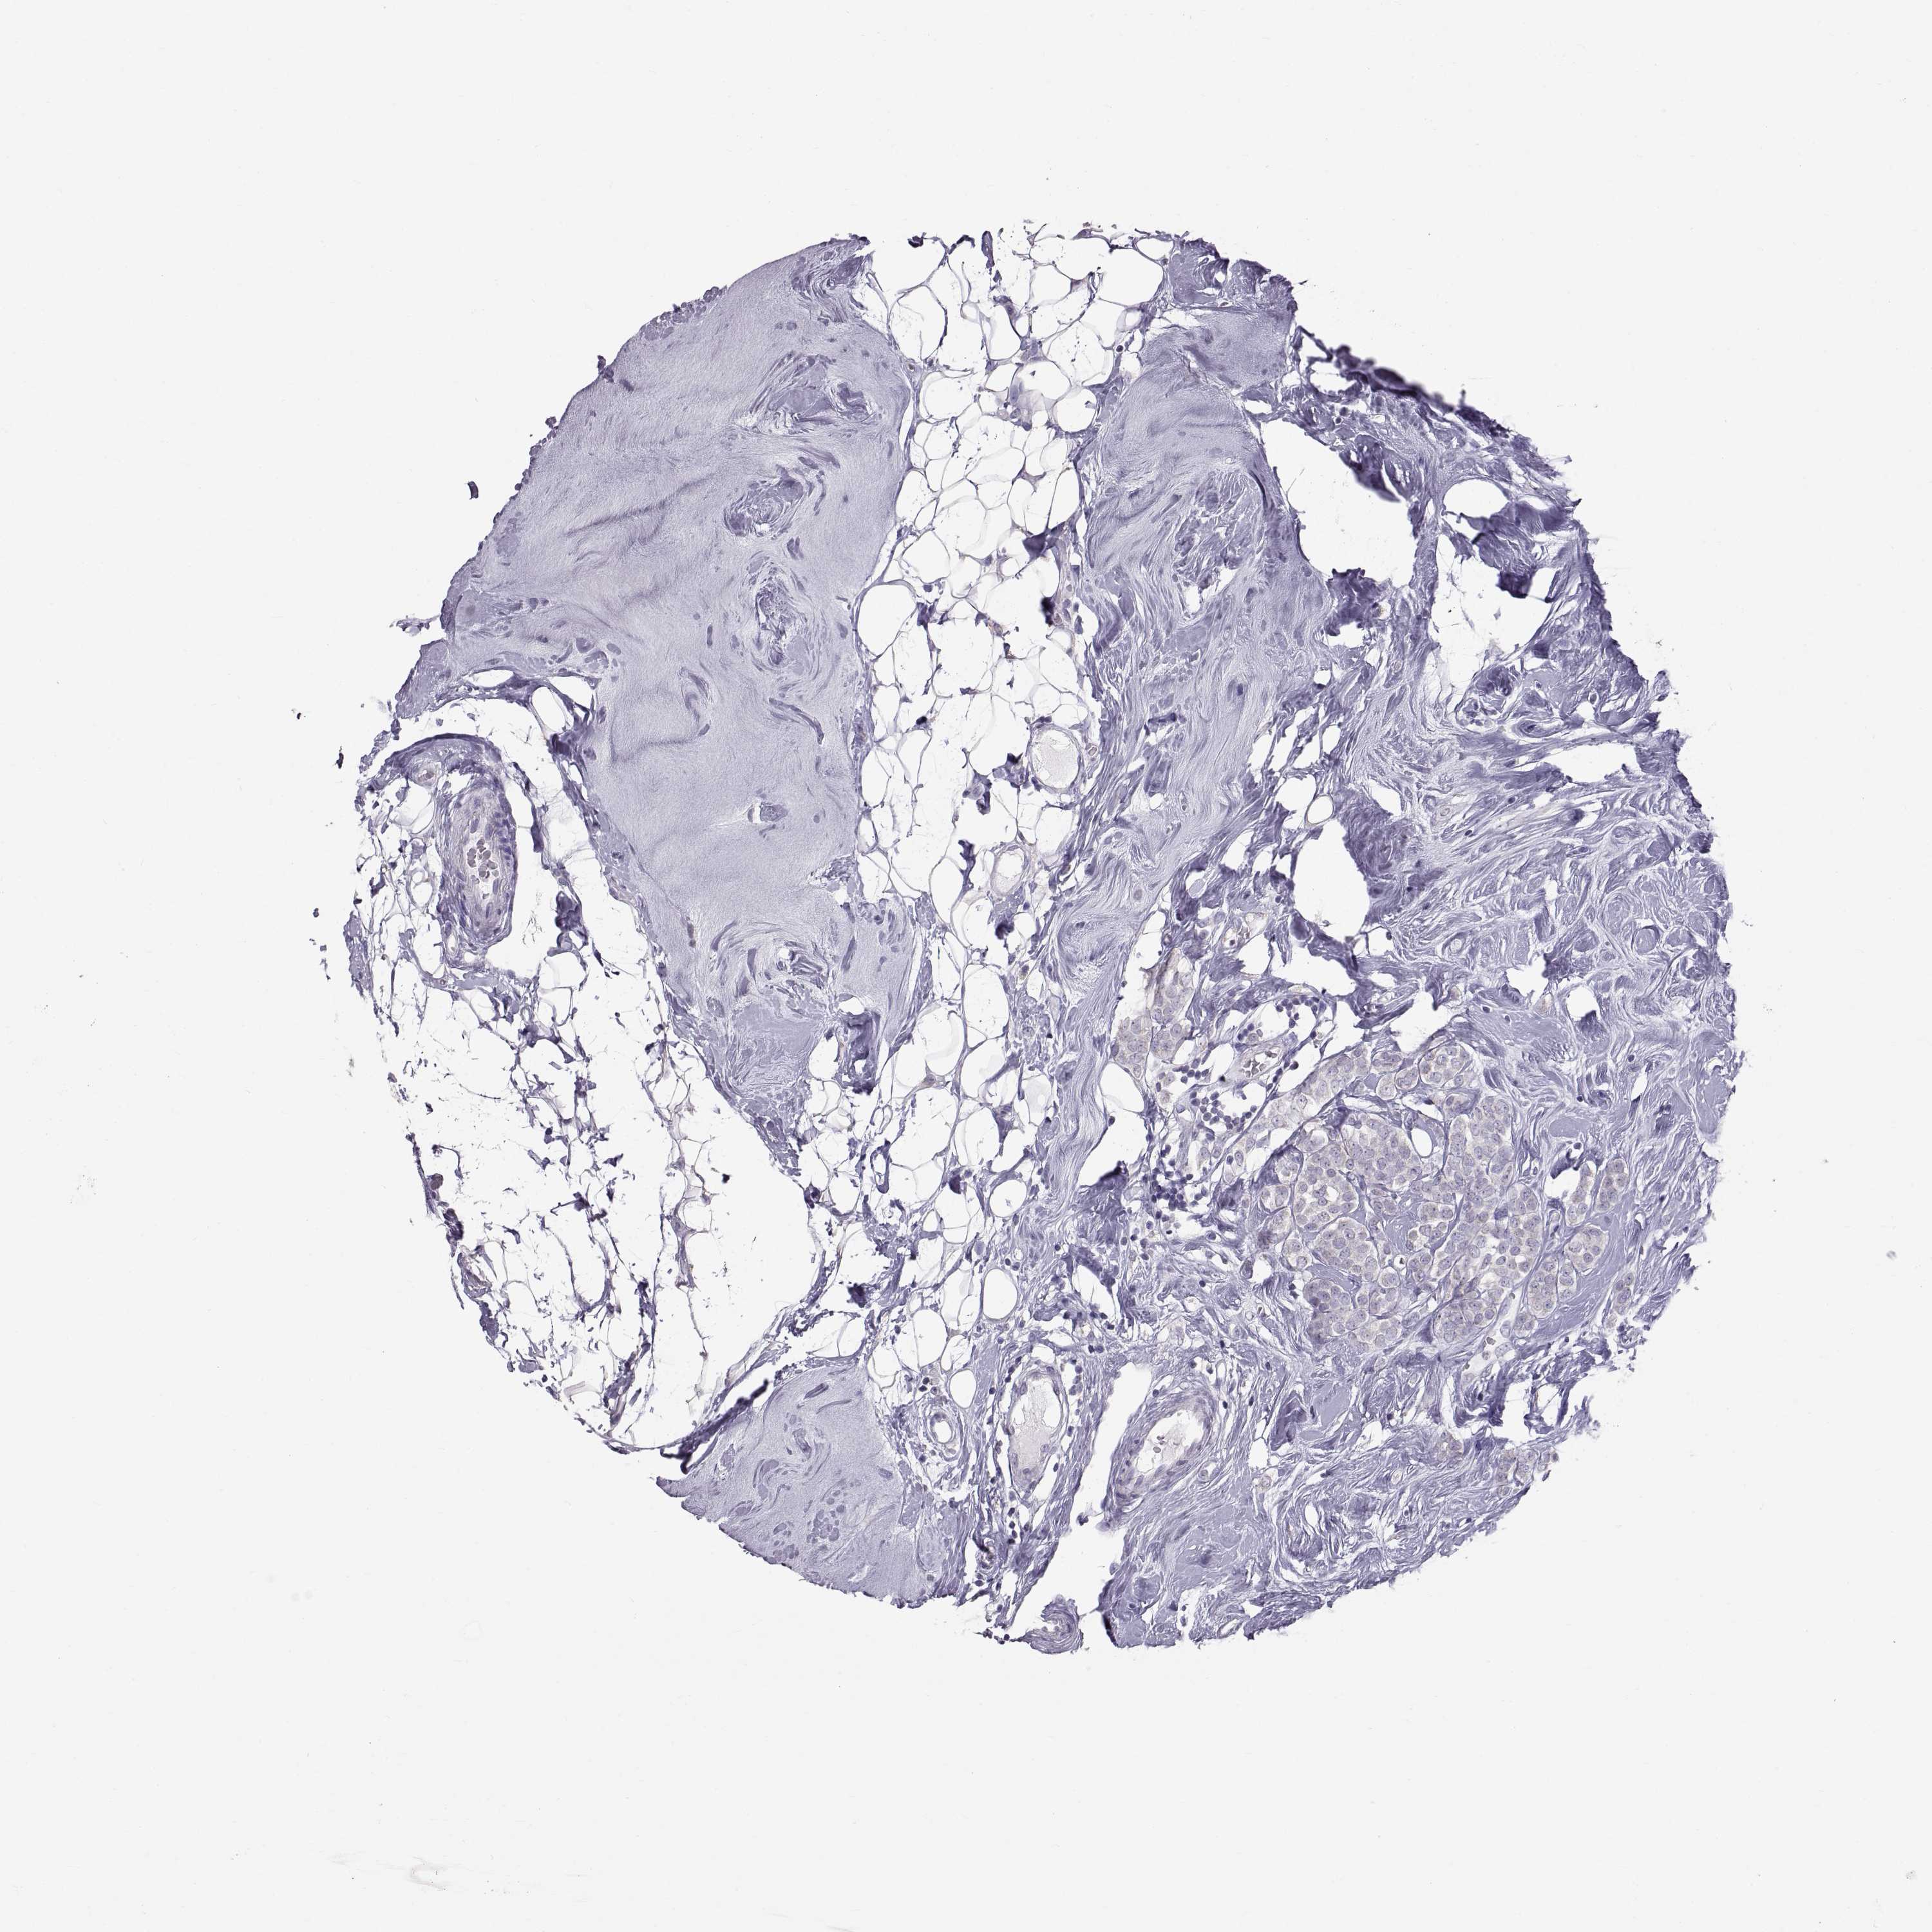

CANCER BREAST CANCER Show tissue menu

BRCA TCGA BRCA VALIDATION PROTEIN EXPRESSION

Breast cancer

Human cancer